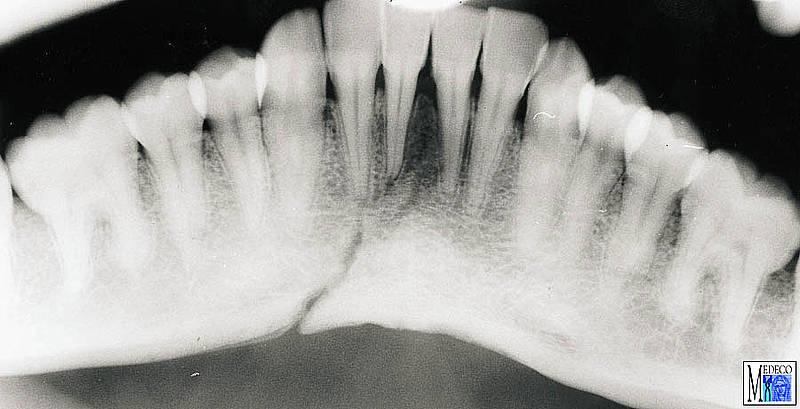

Sfortunatamente, talvolta le radiografie dentali non mettono in evidenza il dente fratturato. Questo molare presenta la sindrome del dente incrinato.

Frattura del processo alveolare from www.medeco.de